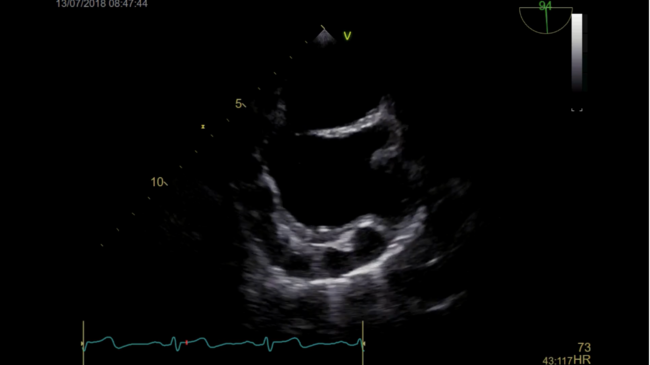

A 60-year-old asymptomatic woman was admitted to hospital for an invasive evaluation of a patent foramen ovale and a suspected formation within the right atrium. The following video series demonstrates a huge “brass knuckle”-like ectasia of the right coronary artery meandering down the lateral wall of the right atrium. In addition, cardiac multislice computed tomography and coronary angiography show a large fistula extending from the left circumflex artery to the coronary sinus.